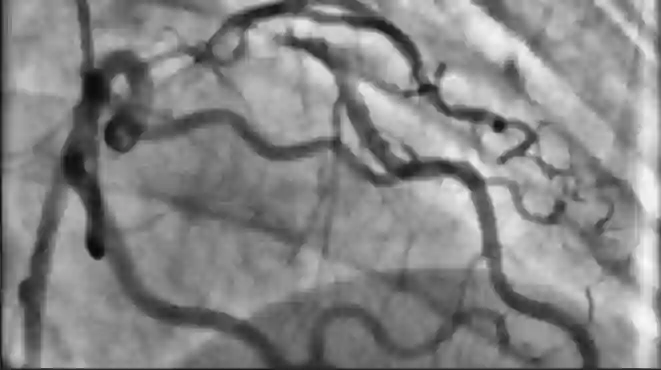

接着上一个问题,对于绝大部分计算机视觉项目来说,客户的数据我们真不一定能看懂。比如医疗影像,数据标注是医生都需要经过多年培训才能做好的事情,没有任何医疗背景的程序员很难在短时间内看懂这些数据。年初的时候我们给某工厂做缺陷识别,用什么网络什么部署模式都想好了,结果就是看不懂图片不能做标注。我们看所有地方都像是坏了,但工厂的质检员就能一眼分辨出来正常和缺陷。这种行业的 know how 很重要。

心脏造影图,非医务人员很难看出图中哪些是对诊断有帮助的血管